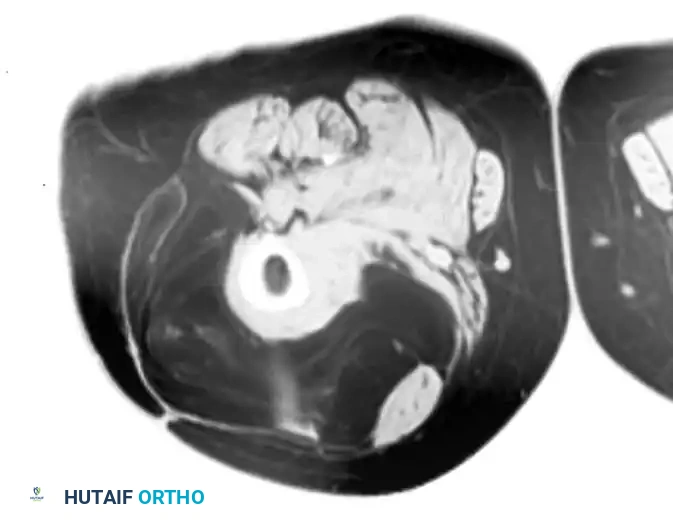

Conventional radiographs may demonstrate a non-specific soft-tissue density but are usually normal. MRI reveals a well-circumscribed mass that is typically isointense to muscle on T1-weighted images and hyperintense on T2-weighted images. Central necrosis is a hallmark of larger, high-grade tumors.

Axial MRI showing a large soft-tissue mass in the thigh with mixed signal intensity, characteristic of UPS/MFH.

MRI is highly specific for well-differentiated variants, demonstrating fat signal intensity (bright on T1, suppresses on STIR/Fat-Sat) with thick, nodular septations.

Contrast-enhanced, fat-suppressed axial MRI of the same lesion. Note the multiple thick, enhancing septa distinguishing it from a benign lipoma.